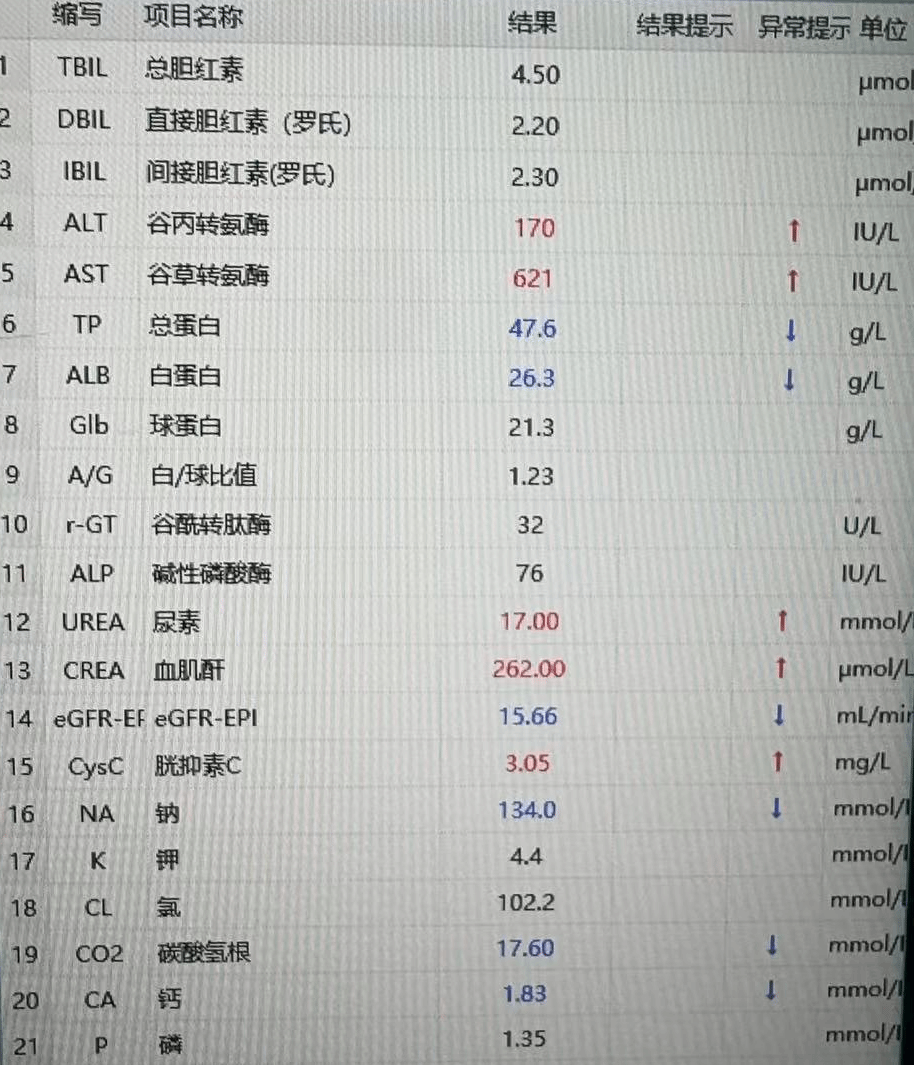

患者术前造影患侧肢体血管完全不显影

开通后的患侧动脉造影